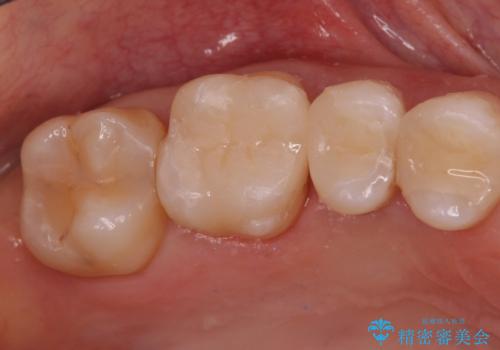

[e-maxインレー] 矯正治療前の虫歯治療

- 矯正治療前の患者様です。

う蝕があったのでe-maxインレーにて治療しました。

- e-maxインレー 7.7万円 費用は治療当時の料金となります

う蝕があるままで矯正を始めてしまうと矯正治療中にう蝕が悪化する可能性があります。矯正治療を行う前はう蝕や歯周病がある場合にはしっかり治療を行なってから矯正治療がスタートします。

![[e-maxインレー] 矯正治療前の虫歯治療の治療後](https://seimitsushinbi.jp/wp/wp-content/uploads/2023/08/IMG_2869-1-500x350.jpg?v=1691812292)